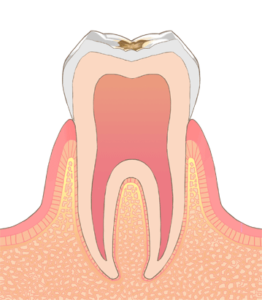

虫歯の進行段階と治療の流れ

C1段階 − 小さく削って詰める

治療は1〜2回で終わることが多く、治療は必要に応じて型取り、虫歯の除去、詰め物を充填、研磨の手順で行います。

C2段階 − 削って詰める

むし歯が大きい場合は銀歯(保険)、金歯、セラミックといった詰め物

を歯の一部に入れることになります。

C3段階 − 神経をとって被せる

むし歯が神経にまで達している場合は、神経をとって、根の治療をした上で歯に土台を立て、その上から歯を模した被せもの(こちらも銀歯(保険)、金歯、セラミックなどがあります)を入れることになります。

C4段階 − 抜歯

この状態になると、歯を抜かないといけなくなることが多いです。歯の詰め物や被せ物には先ほど述べたような種類があり、ご自身がどのようなお口でいたいか、どのように治療したいかによって選択することができます。(これ以上むし歯ができて欲しくない、自分の元の歯のように綺麗にしたい、費用を抑えたい、などです)